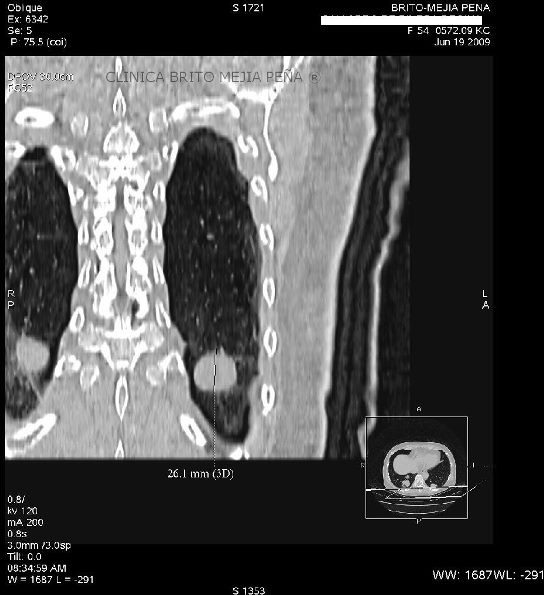

Trombosis arteria pulmonar coronal